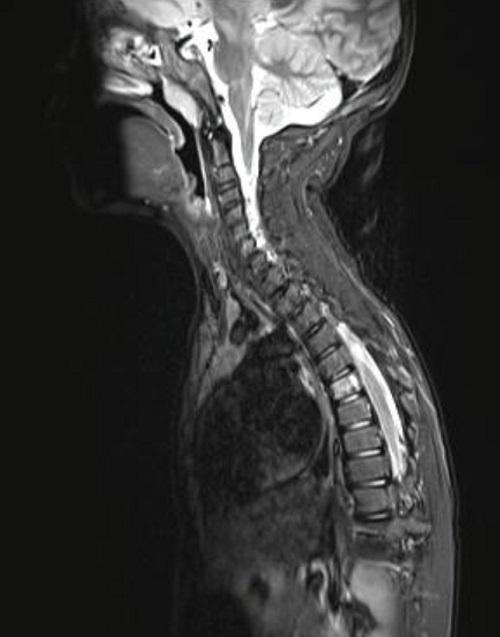

Dos meses después de la intervención quirúrgica, por algias en región dorsal, se realiza tomografía por emisión de positrones (PET/TAC) donde se aprecian las 2 lesiones ya conocidas en hueso parietal izquierdo y se detecta un foco hipermetabólico con gran intensidad de captación en lesión lítica situada en hemicuerpo izquierdo de D6. No se encuentran otros hallazgos en el resto del esqueleto ni en partes blandas, vísceras o ganglios linfáticos. La RMN confirma el hallazgo y se aprecia una lesión en D6, inespecífica, osteolítica, con algunos focos de esclerosis periféricos, compatible con hemangioma vertebral sin poder descartar GE en el contexto del paciente. La presencia de edema óseo perilesional iría a favor de GE (Figura 4).

Figura 4. Resonancia magnética nuclear

El Servicio de Hemato-Oncología del hospital de referencia, junto con los padres, decide iniciar tratamiento con indometacina, a 2 mg/kg/día. Desde entonces, el paciente se mantiene asintomático y en los controles de imagen periódicos se va notando reducción de las lesiones. Diecinueve meses después del inicio del tratamiento realizan nueva RMN que muestra ausencia de resto o recidiva de su patología de base: defecto óseo parietal izquierdo ya conocido y estable. Práctica resolución de la lesión en la vertiente izquierda del cuerpo de D6 (Figura 5). Ante estos hallazgos se decide retirar el tratamiento, permaneciendo asintomático cuatro meses después de la suspensión del mismo.

Figura 5. Resonancia magnética nuclear vertebral